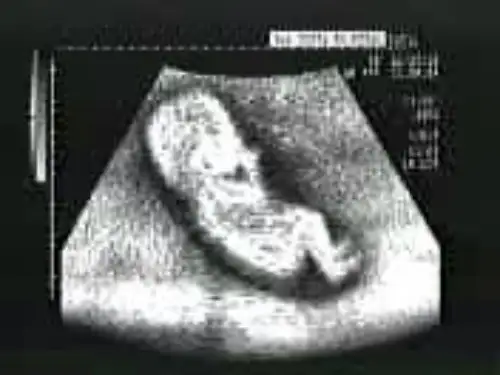

Ultrasonography of intrauterine fetus

中、晚期妊娠超声表现

1.羊膜囊逐渐充满宫腔,妊娠囊消失 2.可清晰显示子宫内胎儿(胎头、脊柱、胸部、腹 部及肢体)、羊水、胎盘